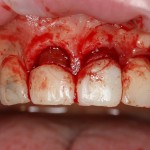

Давайте внимательно посмотрим на состояние лунок центральных резцов после удаления:

Приемлемый фенотип (сочетание толщины и ширины участка жевательной десны) — это, конечно, приятно. Но гораздо важнее сосредоточиться на рисках, их на этот момент два:

— травматическое повреждение слизистой, вызванное удаление зубов связано с тем, что при хроническом воспалении слизистая оболочка теряет эластичность, поэтому легко рвётся. Такая ситуация создаёт серьёзную угрозу эстетическому результату лечения, в зависимости от того, насколько быстро десна придёт в норму.

— как и предполагалось после КЛКТ, утрата костной стенки привела к тому, что десна провалилась в просвет лунки левого центрального резца. Это еще больше усугубляет клиническую ситуацию.